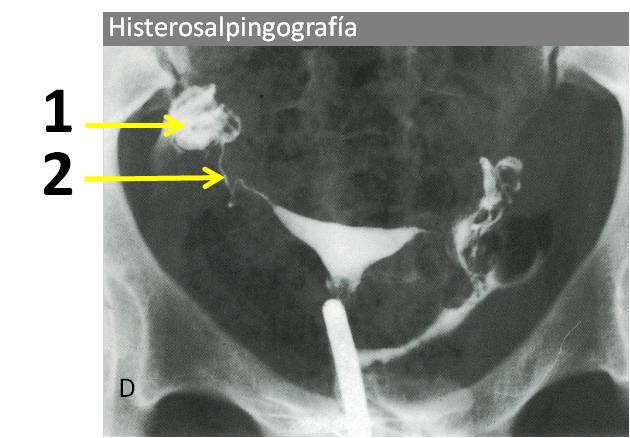

} Identifique las estructuras señaladas:

_Identifique las estructuras señaladas

" Identifique las estructuras señaladas

; Identifique las estructuras señaladas:

& Identifique las estructuras señaladas